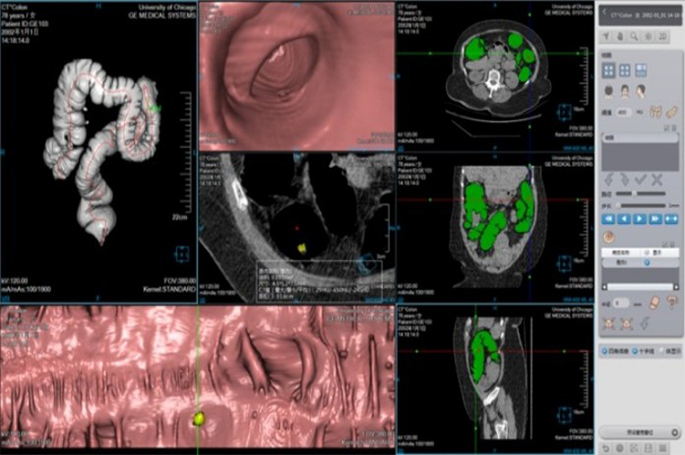

Inspiration 128 slice CT scanner designed to deliver exceptional high-end image quality, efficiency, and versatility. This cutting-edge system satisfies a wide range of clinical contexts

Multiple Clinical Scene